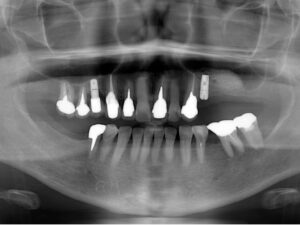

1.患者様の主訴:左上にインプラントを入れたい

2.診断結果:

左上の奥の骨の厚みが薄いため上顎洞を挙上する必要がある

3.治療内容:

上顎洞挙上術を行なって6ヶ月経過したのちにインプラントを入れた

写真は治療前骨の厚みが1mm以下だったところ、上顎洞挙上術で1cm程度の骨の厚みになり、9mmのインプラントを入れた。その後半年待ってから上部構造を入れた。

5.治療期間:1年

6.治療費用:

CT診断¥22,000+上顎洞挙上術¥165,000+臼歯インプラント440,000×3本=¥1,507,000

7.リスク・副作用:上顎洞粘膜の穿孔、術後の脹れ